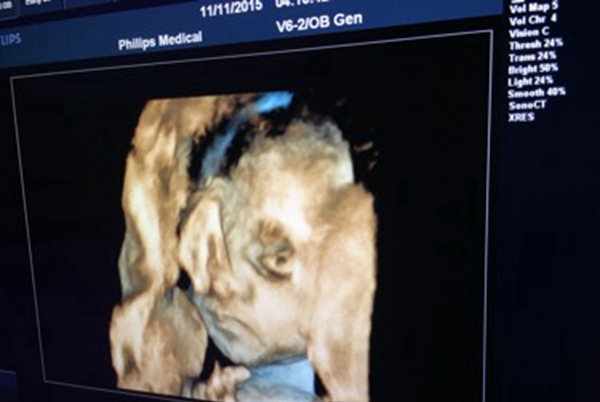

导语:普遍来说家里核心有新性命出身是一件很痛快的事务,然而是广州别名女子生下儿童却不那么让人喜悦,本来儿童从出身起便不睁启眼睛,厥后医生说他患上了无眼症。

天才不眼睛真实很让人懊恼,而无眼症该当是一种比拟少睹的基因疾病,这也是一种反常纵然查过b超也很难创造。博家以为该疾病大概是基因渐变引起的,大概者说妊妇在怀胎初期,胚胎爆发了某些奇异的变革,这些都是没措施阐明的。

儿童也和其余方才方才出身的普遍绚烂,他也会动来动去连交哭闹,除了眼睛除外其余都是平常的。无眼症这个疾病也是很残酷的,天才不眼睛的儿童以来生计真实艰巨得多。

无眼症是一种很少睹的疾病,有着很矮的发病率,一些患儿缺乏局部眼球,有些直交不眼球,这种疾病很难经过B超创造。该患儿家人也说了产妇都保持举行体检,都没创造什么不关于劲的,没料到儿童会如许。

而儿童的家人也去预定了博业的三甲病院,决断给儿童一个浑身查瞅,躲免身材有其余缺点不被创造。并且儿童的家人说关于于如许的儿童真实很难保持。究竟他从出身便表示不大概瞅到这个世界了,真实十分惨苦。那么怎么样躲免儿童反常,孕期排畸十分要害。